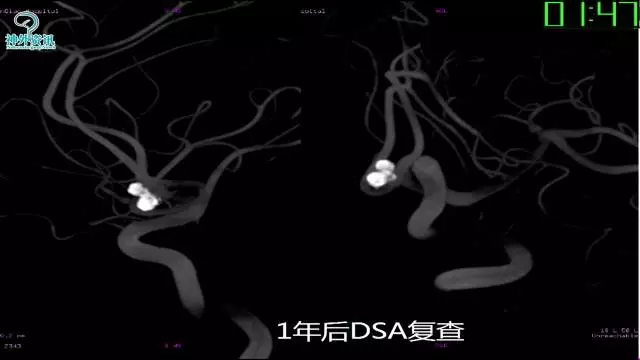

今天为大家分享的是“强生医疗CNV-神经介入专栏”第三十六期,由重庆第三军医大学附属新桥医院神经外科刘俊带来的“Galaxy弹簧圈在不规则动脉瘤中的临床应用”精彩讲课视频及PPT,欢迎观看。文章仅代表作者个人观点,如有不同见解,欢迎同道斧正!